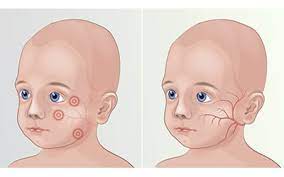

قیمت: 45٬000 تومان - دسته بندی فایل: پاورپوینتدانلود پاورپوینت سندروم جانسون بلیزارد

جدیدترین و ارزانترین فایل پاورپوینت با عنوان پاورپوینت سندروم جانسون بلیزارد تعداد اسلاید: 25